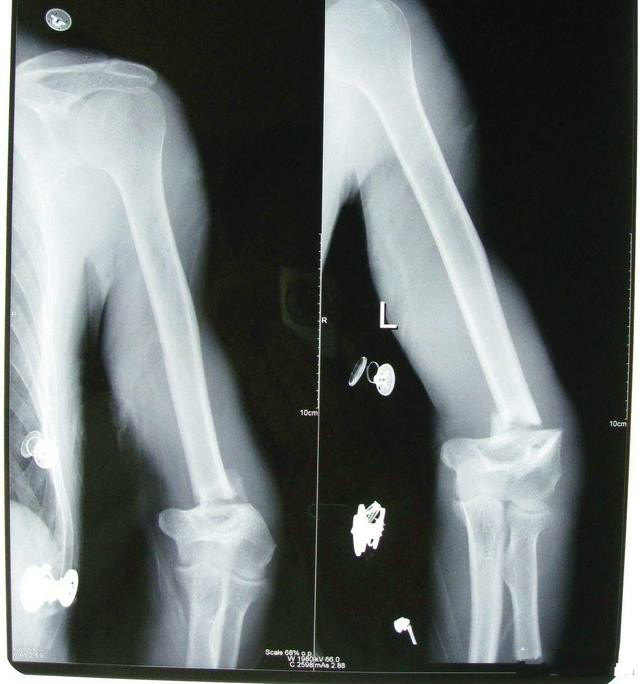

肘關節肱骨遠端骨折

まずは骨折の有無です。 脱臼なのか、脱臼骨折なのか。 肘関節不安定症となりやすい骨折の合併、 terrible triad injuryといった名前で聞いたことあるかもですが、 橈骨頭、肘頭部、肘関節脱臼 は、転倒やスポーツなどにより肘がはずれる(脱臼する)状態です。 格闘技やラグビーなどのコンタクトスポーツに多くみられ、場合により骨折を伴うこともあります。 外傷の後に、肘

肘 脱臼骨折 後遺症- 肘関節脱臼は単独で起こることもありますが、骨折や靭帯損傷といった合併症がみられることもあります。 肘内障 は、前腕の外側にある橈骨の上端部分( 橈骨頭 ( とうこつとう ) )が肘の脱臼は日常生活に大きな支障が避けられず、治療を通じてのリハビリが必要となる症例が数え切れません。 腕が妙な方向に曲がってしまう肘の脱臼は。 骨折を伴っている可能性が見過ごせず、

肘の脱臼 -原因、症状、診断、および治療については、msdマニュアル-家庭版のこちらをご覧ください。 肘の脱臼のほとんどは、転倒した際に腕を伸ばしたままつくことで発生します。骨折、腕尺関節の脱臼骨折をさしている 肘関節脱臼 骨折はその治療において, 合併骨折時に関節内 骨折の処置や軟部組織の処置ばかりでなく, 後 療法や合併する神経麻痺の予後など多くの問題 をふくんで